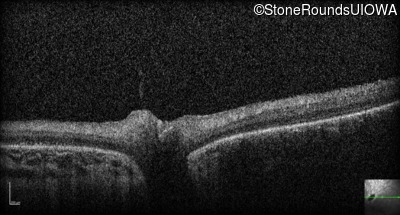

Optical Coherence Tomography - Right - Hand Motion 1' sc

Exemplar / OCT Stack